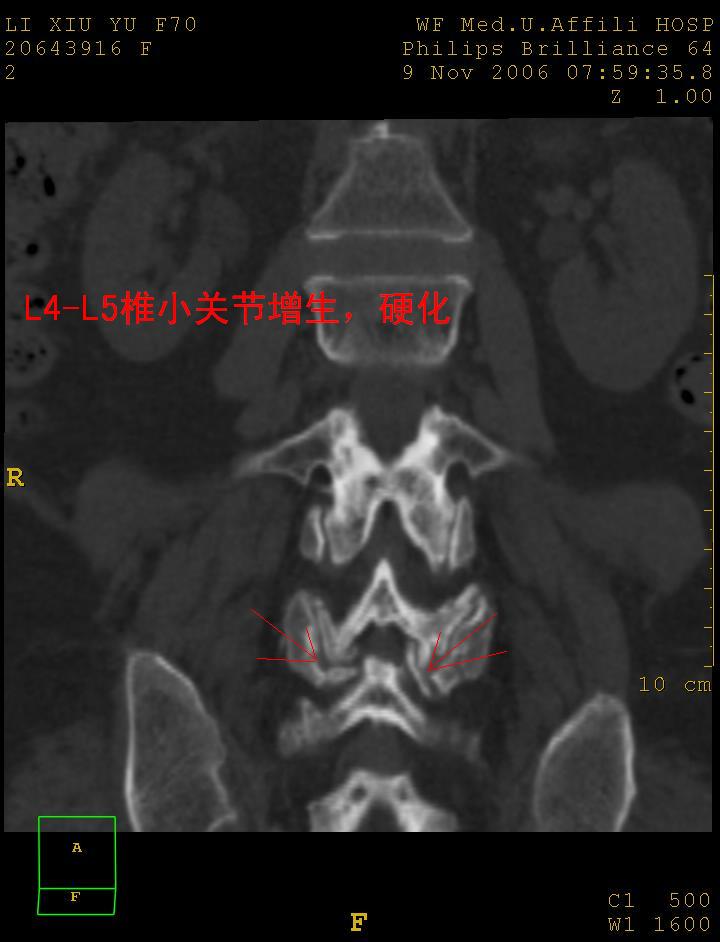

女,70岁,腰痛

1 腰4椎弓崩裂,腰4椎体向前ι度滑脱并椎小关节交锁,腰4/5小关节明显增生硬化,间隙内可见真空征。

2 腰椎间盘不同程度膨出,腰4/5、腰5/骶1椎间盘突出,腰4/5椎间隙变窄,腰5/骶1间盘变性(间隙内可见真空征)。

诊断:腰椎退行性骨关节病。